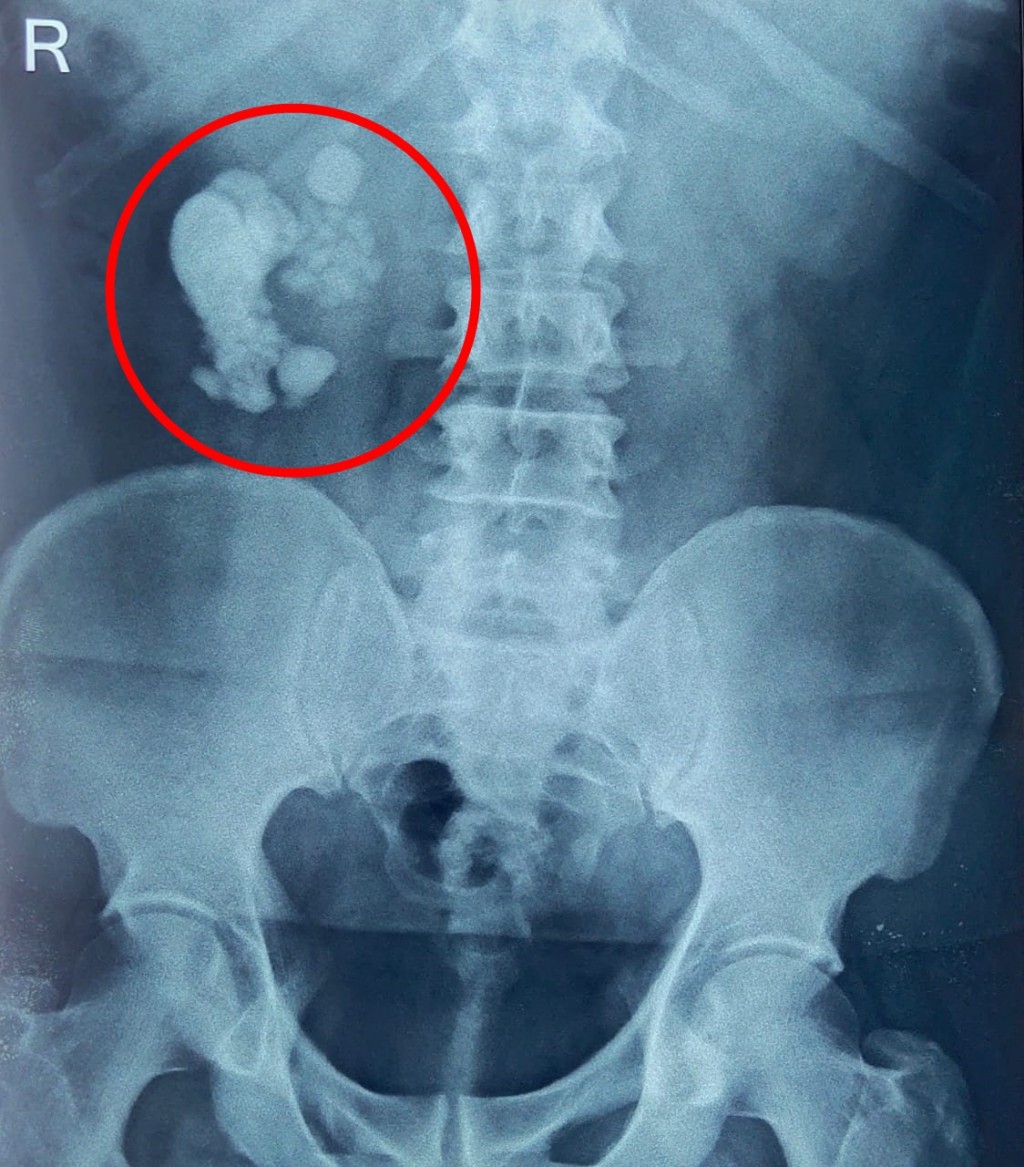

從X光片可見,病人有大量腎石(紅圈)。互聯網圖片

印度一位教師腹痛就醫,意外發現有大量腎石。醫生花了3小時,才將156顆結石全數取出,男子術後已康復出院。

患者為一位50歲的教師,因腹痛前往醫院就診,經檢查後發現腎臟中藏有156顆腎結石,此後他亦患有先天性異位腎。醫生評估後,使用腹腔鏡與內視鏡進行手術,耗費3小時才將結石全數取出。